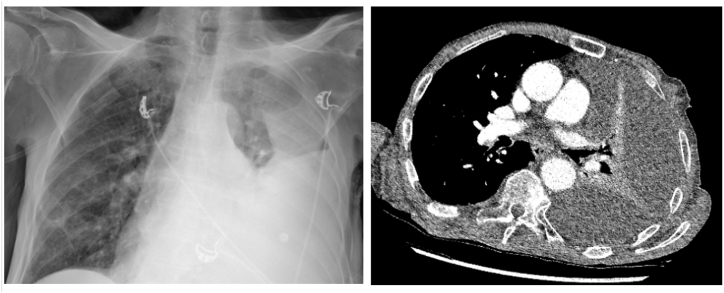

Pancreatopleural fistulas, rare complications of chronic pancreatitis, are often overlooked in the initial differential diagnoses of pleural effusions, resulting in delayed diagnosis and management. We present the case of an elderly male with recurrent pleural effusion and a history of chronic pancreatitis. Diagnostic challenges arose, with the initial misdiagnosis as pneumonia. Elevated pleural fluid amylase levels (11,370U/L) along with imaging findings led to the diagnosis of a pancreatopleural fistula. This case underscores the importance of considering uncommon etiologies in pleural effusions and highlights the significance of high pleural fluid amylase levels in diagnosing pancreatopleural fistulas.